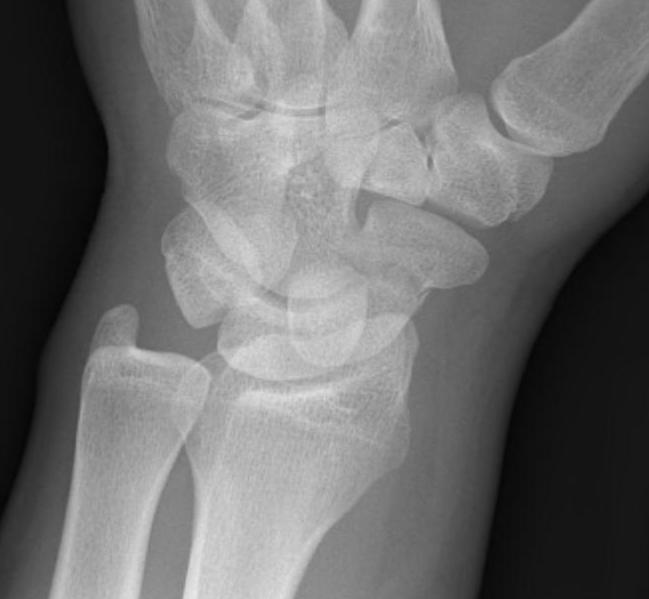

Scaphoid fracture with significant displacement

CT

Indication: any potential displacement

Instability

- displacement > 1mm on any film

- intra-scaphoid angle > 35o

- comminution

- proximal pole fractures

- perilunate trans-scaphoid dislocation